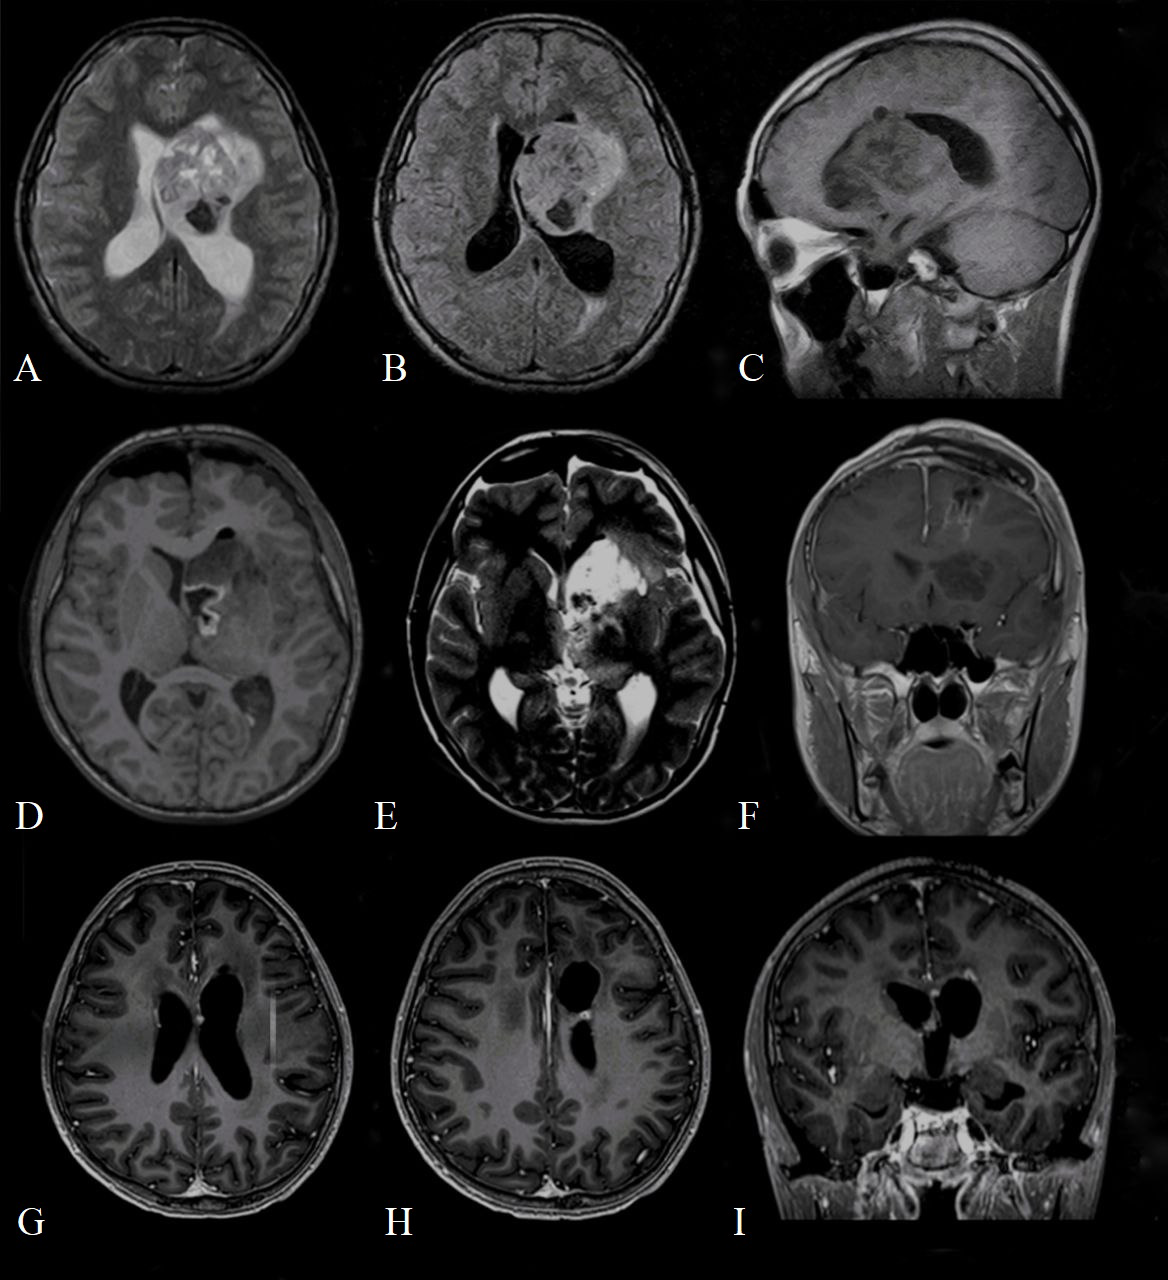

The first cranial MRI (before neurosurgery) reported a contrast-enhanced mass in the left periventricular region with involvement of the left basal ganglia, head of the caudate nucleus, thalamus, until the frontal lobe and body of the lateral ventricle (Figures 1A–C). The lesion (6.8 x 4.4 x 5 cm) consisted of a cystic/solid formation with heterogeneous structure due to areas of hemorrhage; it was hypointense on T1-weighted images, hyperintense on T2-weighted images; it showed irregular borders and was surrounded by a rim of edema. The mass compressed the left lateral and third ventricles, and the midline structures of the brain were displaced to the right, indicating asymmetric internal hydrocephalus. Spinal cord imaging did not show any changes.

Preoperative (A) T2 axial magnetic resonance imaging (MRI); (B) T2 FLAIR axial MRI; (C) T2 sagittal MRI demonstrating mass in the left lateral ventricle with heterogeneous enhancement measuring 7.2 cm x 4.7 x 5 cm, composed of both cystic and solid areas, and extending to the frontal lobe of the brain; Postoperative (D) T1 axial magnetic resonance imaging (MRI); (E) T2 weighted image axial MRI; (F) T1 contrasted coronal MRI demonstrates the area of postoperative cystic change and residual tumor measuring 1.3 cm x 1.1 x 1 cm, actively accumulating contrast agent; contrasted T1 axial (G, H) and coronal (I) MRI at 17-month follow-up, which shows residual tumor measuring 4.5 x 3.2 mm (H) and 4.3 x 2.6 mm (G).

The computerized tomography (CT) obtained in the immediate postoperative period showed foci of air and small areas of hemorrhagic component along the periphery of the surgical bed. Brain MRI performed on the 2nd day after surgery showed a residual tumor measuring 1.3 x 1.1 x 1 cm in the region of the left lateral ventricle (Figures 1D–F).

However, after additional histopathological examination and molecular analysis, the final diagnosis of AT/RT was made. After multidisciplinary consultation, the patient underwent radiation therapy: he received a total of 34 Gray (Gy) in 17 fractions to the craniospinal axis and an additional sequential boost of 20 Gy in 10 fractions to the residual tumor. The patient developed leukopenia and thrombocytopenia, which required transfusion therapy and a 3-day course of filgrastim. He otherwise tolerated the radiation therapy regimen well. An adjuvant chemotherapy regimen was started (shortly after radiotherapy) and consisted of vincristine 2mg/m2, etoposide 100mg/m2, cisplatin 90mg/m2, cyclophosphamide 300mg/m2, doxorubicin 30mg/m2, actinomycin D (dactinomycin) 0.015mg/kg or 1.2mg/m2 (depending on chemotherapy cycle) and temozolomid 200mg/m2 administered over 14 cycles. Additionally, during each course of chemotherapy, the patient received intrathecal chemotherapy, consisting of methotrexate 15mg/m2, cytarabine 60mg/m2, prednisolone 30mg/m2. The patient well tolerated all these 14 cycles of adjuvant chemotherapy without any major complications. After 7 months since the diagnosis, MRI showed a decrease in the size of the residual tumor. At 21 months’ follow-up, the patient is alive and a further decrease in the size of the residual tumor was shown (Figures 1G–I).